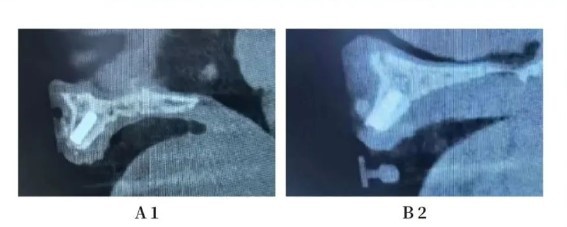

Radiological Examination - Preoperative CBCT

Sagittal section reveals bone deficiency in the labial wall near the mesial aspect of A4 and on the buccal side of A3, while the lingual wall remains intact. Adequate bone volume is observed for A2 and B2.